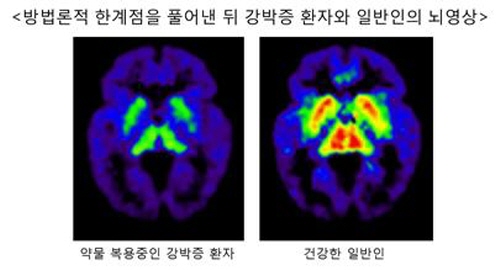

분당서울대학교병원 정신건강의학과 김의태 교수팀은 건강한 일반인 12명과 약물 치료중인 강박증 환자 12명의 뇌 PET을 각각 수십 차례 촬영해 비교하는 연구를 진행했다.

김의태 교수팀이 약물 농도 변화와 강박증의 치료 핵심이 되는 환자의 세로토닌 수용체의 밀도를 계산한 결과 약물치료로 증상이 호전됐던 강박증 환자에서 여전히 세로토닌 수용체의 밀도가 낮았음을 확인할 수 있었다.

이는 증상이 호전되더라도 약물치료를 중단하지 말고 세로토닌 시스템의 이상이 정상이 될 때까지 일정기간 약물치료를 지속해야한다는 사실을 보여준다.

연구를 주도한 분당서울대학교병원 정신건강의학과 김의태 교수는 “약물 치료로 증상이 호전되더라도 실질적으로 강박증의 원인이 되는 세로토닌 시스템의 이상은 교정되지 않았던 것”이라며 “이번 연구는 이전까지 불가능했던 강박증 약물 치료의 한계점을 풀어냈다”고 설명했다.